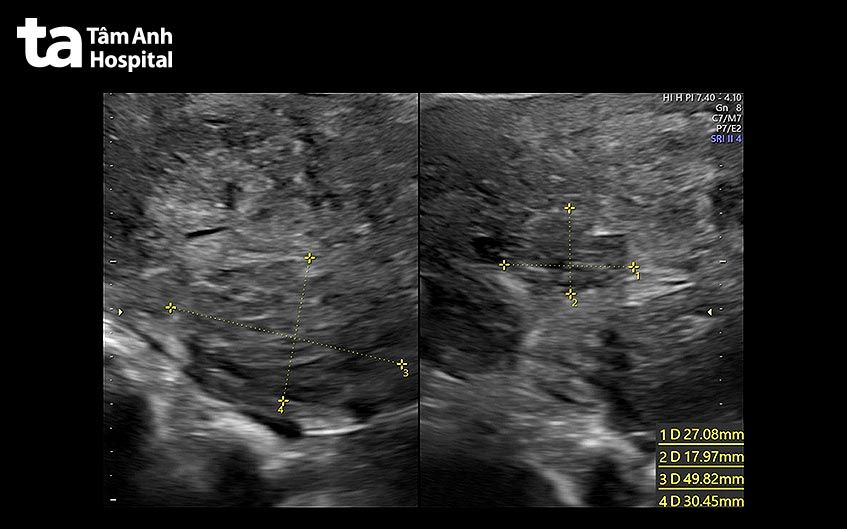

Ngày 18/7, BS.CKII Nguyễn Bá Mỹ Nhi, Giám đốc Trung tâm Sản Phụ khoa, BVĐK Tâm Anh TP HCM cho biết, chị Lý 48 tuổi, đã mổ bóc u xơ tử cung cách đây 18 năm, nay bệnh tái phát khiến tử cung to như mang thai 18 tuần, kèm theo khối u lạc nội mạc tử cung vào buồng trứng. Tháng 12/2023, chị nhập viện do có huyết khối tĩnh mạch não, được bác sĩ dùng thuốc kháng đông ngừa huyết khối.

Ngày 9-7, bác sĩ Mỹ Nhi và ê kíp thực hiện ca phẫu thuật cắt tử cung, loại bỏ khối u xơ tử cung. Sau mổ, chị không còn tử cung, không hành kinh, sẽ giảm đau đớn. Ca mổ khó do bệnh nhân sử dụng kháng đông kéo 7 tháng, nguy cơ chảy máu trong cuộc mổ rất cao, rê kíp bóc tách, đốt cầm máu kỹ. Sau khi vào lớp bụng, bác sĩ quan sát tử cung to tương đương thai 18 tuần, đưa ra ngoài khó khăn, ổ bụng có sẹo mổ cũ, các quai ruột dính vào tử cung, khó tách dính, nguy cơ thủng ruột. Sau 2 giờ phẫu thuật, bác sĩ cắt bỏ tử cung thành công, chỉ mất khoảng 300ml máu, ít hơn một cuộc chuyển dạ đẻ thường.